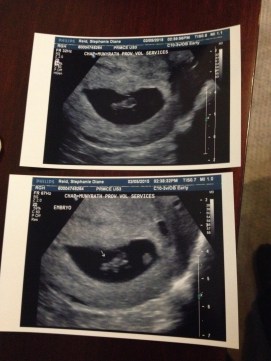

When I finally started to sort through them, the first thing I pulled out was an envelope. It wasn’t labeled and I didn’t know what was inside. I opened it up and saw my first ultrasound pictures of Blake. I was quickly taken back to a time of excitement. It’s amazing, how a picture can take you right back to the feeling at that moment. I remember that first ultrasound so vividly. Jeff and Kenley were with me. Kenley was so little, she was drinking a bottle. She was wearing the cutest pair of pants; they were lavender, with thin little stripes and a bird on the buns. All three of us looked at the screen in awe. Obviously, Kenley’s awe was different than ours! Blake was bouncing around in there, looking like a little gummy bear.

That was the first time I heard someone call Kenley a big sister. I remember thinking how silly that sounded, since she was still a baby herself. Jeff was so excited to see the heartbeat. His face was the same with every ultrasound we had with both of our girls; smiling, ear to ear, the entire time. Really, it was just the best day.

Sometimes- well, most times- it’s a struggle to remember life before SMA. Even before Blake wasn’t officially diagnosed, I always felt something wasn’t right. From the day she was born, there really wasn’t a time when I wasn’t worried about her. Those ultrasound pictures take me back the very beginning of my pregnancy. My thoughts were focused on things like napping in the car during my lunch break, or what life would be like as a family of four; which crib to pick out and how to create another nursery in our house.